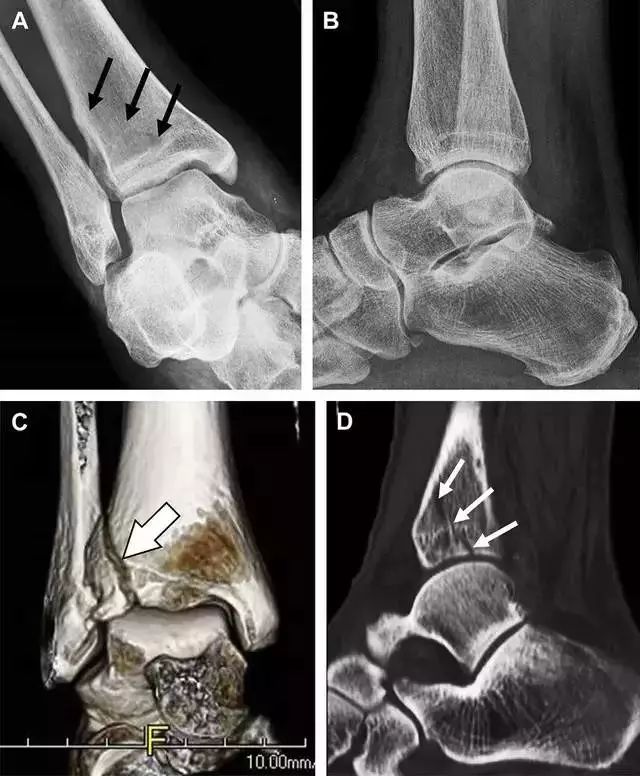

Tillaux 骨折,是足外旋外展时,胫腓前韧带牵拉引起的一种胫骨结节撕脱性骨折。斜位片上可见典型表现(图 3)。

图 3 摔倒后胫骨结节骨折。A 正位片示一细小斜型骨折线(箭头);B 侧位片示正常;C 冠状位 CT 三维成像更清晰地显示了骨折线和骨折块大小(空箭头);D 矢状位 CT 多维重建图像示骨折位置(箭头)。

距骨外侧突骨折

距骨外侧突骨折常因踝外翻背屈时,跟骨上外侧面撞击距骨外侧突下缘导致,或偶尔由踝内翻引起,被称为「滑雪板者骨折」。这种骨折只能在踝关节正位片上发现,而且外踝远端表面软组织肿胀往往是一个重要线索(图 4)。

图 4 距骨外侧突骨折。A 正位片示内翻损伤所致的距骨外侧突撕脱性骨折(箭头);B 另一位患者,踝外翻损伤导致典型的「滑雪板者骨折」,X 片上可见一较大的三角形骨折块(方框);C 第二位患者的 MRI 矢状位 T1 加权像示横行骨折(箭头)。

距骨后突骨折

距骨后突有内侧结节和外侧结节,距骨后突内侧结节撕脱性骨折常发生在背屈内旋的*力暴**作用下。严重跖屈时,胫骨后缘和跟骨挤压距骨后突外侧结节呈楔形,易发生粉碎性骨折。这些骨折细微且需与三角骨鉴别。侧位片观察距骨后突骨折最佳,常规拍片很难发现,当高度怀疑这种骨折又没法做 CT 时,建议加做多个角度的外旋斜位片(图 5)。

图 5 距骨后突骨折。侧位片(A)和 MRI 矢状位 T1 加权像(B)均示后外侧突的简单骨折(箭头),再次阅片时才发现 X 线片上的骨折;侧位片(C)和 CT 横断面图像示后内侧突的粉碎型骨折(箭头)。